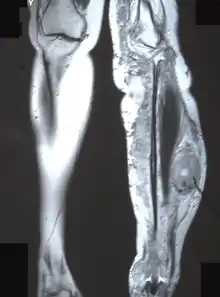

- Unilateral overgrowth of a limb. When a plexiform neurofibroma manifests on a leg or arm, it will cause extra blood circulation, and may thus accelerate the growth of the limb. This may cause considerable difference in length between left and right limbs. To equalize the difference during childhood, there is an orthopedic surgery called epiphysiodesis, where growth at the epiphyseal (growth) plate is halted. It can be performed on one side of the bone to help correct an angular deformity, or on both sides to stop growth of that bone completely. The surgery must also be carefully planned with regard to timing, as it is non-reversible. The goal is that the limbs are at near-equal length at end of growth...